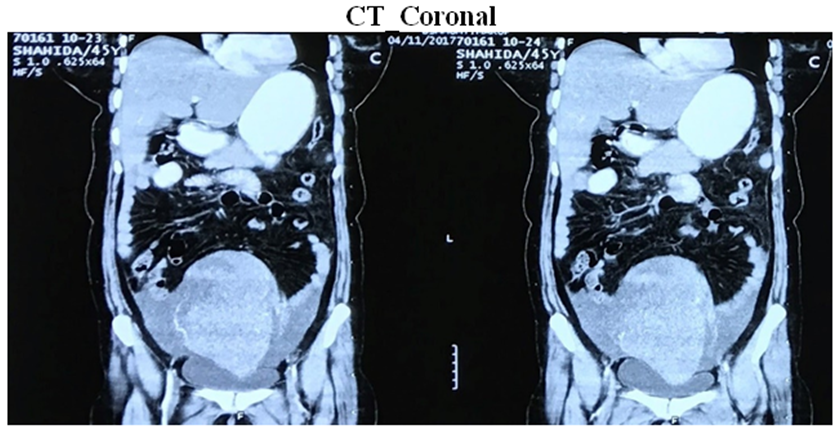

Primary Ovarian Non-Hodgkin’s Lymphoma with Late Diagnosis Due to Unusual Presentation - A Case Report

Involvement of NHL in ovary is seen in disseminated Lymphoma but primary ovarian lymphoma still not commonly seen. We presented the case where the patient had suffered for unexplained fever …

Treated with R-CHOP protocol for 6 cycles as IHC expressed CD20 positive. Post chemotherapy follow up PET scan showed complete response of treatment, though in …